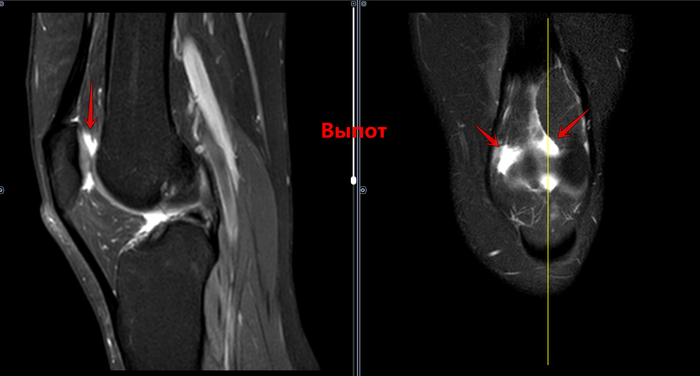

Описание: В структуре внутреннего мениска левого коленного сустава определяется линейный продольный косогоризонтальный патологический МР-сигнал от повреждения с распространением на дистальную суставную поверхность в области тела, заднего рога (соответствует IIIа ст. по Stoller). В области заднего рога медиального мениска определяется многокамерная киста, размерами 1,6х0,7х1,5 см.Целостность крестообразых связок сохранена.В области энтезиса сухожилия медиальной головки икроножной мышцы определяется утолщение, разволокнение.В области сухожилия полуперепончатой мышцы определяется многокамерное жидкостное образование неправильной формы, размерами 1,0х2,8х4,0 см (киста Бейкера).Краевых остеофитов нет.Интенсивность сигнала от клетчатки Гоффа без особенностей. Убедительных данных за патологические изменения остальных видимых мягких тканей не получено.

Заключение:

МР картина повреждения внутреннего мениска (IIIа по Stoller) левого коленного сустава; интерстициальное повреждение внутренней коллатеральной связки; энтезопатии сухожилия медиальной головки икроножной мышцы. Умеренный синовит, супрапателлярный бурсит. Киста заднего рога медиального мениска. Киста Бейкера.